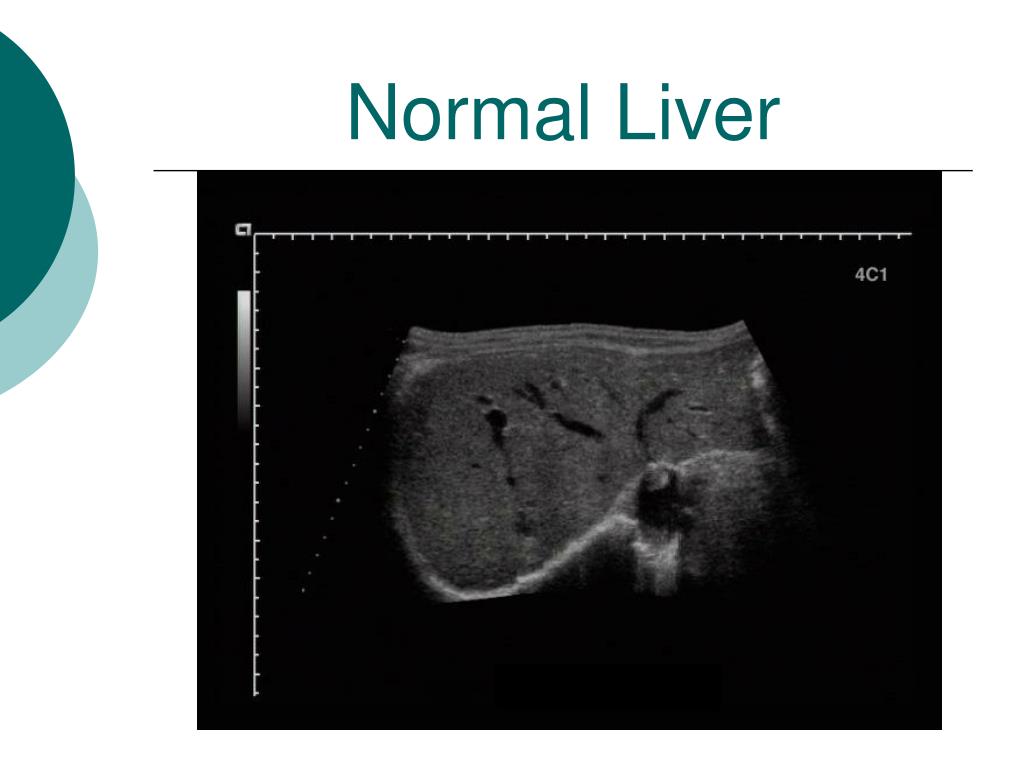

42. Normal Liver